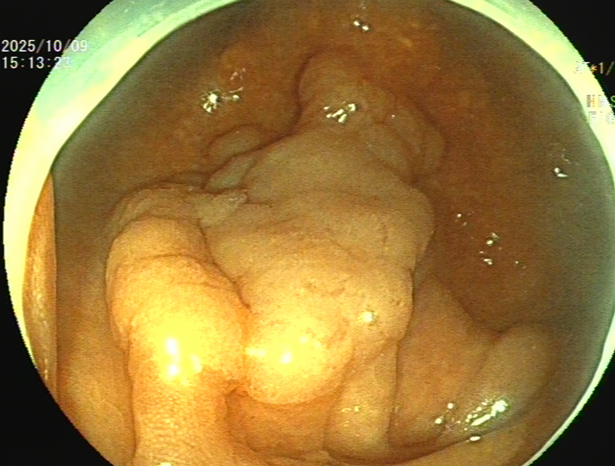

吴姨(化名)平素饮食规则,无腹痛、便血等消化道不适,因其侄女有大肠肿瘤病史,为求安心,特从外地来连州市人民医院进行肠镜检查。消化内镜室吕美光医生在检查中,凭借丰富经验和高清放大染色内镜技术,于盲肠深处发现一个与正常黏膜极其相似、范围达35mmX45mm的平坦微隆起型病灶,并确认其微表面及微血管结构存在异型。后续活检证实,该病灶为盲肠管状腺瘤。

潘新智主任介绍,盲肠侧向发育型肿瘤(LST)是一种发生在盲肠部位的特殊类型的肿瘤,这种肿瘤通常呈扁平状增生,紧贴肠壁,像烙饼一样,具有比普通息肉更高的恶变潜能。由于其特殊的生长方式,盲肠侧向发育型肿瘤在内镜下治疗相对困难,耗时较长,肠道穿孔出血的风险较高,需要医生具备敏锐的观察力和丰富的经验。